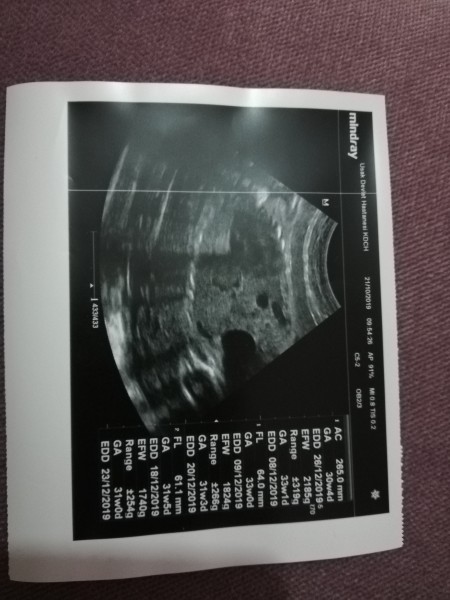

Ultrason Terimleri Hamilelikte Olcumler Crl Bpd Ne Demek Buyurken

Hamilelikte Yapilan Ultrasondaki Terimler Ne Anlama Geliyor Benim Gunlerim

Hamilelikte Ultrasonografi Ultrason Olculeri Degerleri Olcumleri Fetal Biometri Perinatoloji Biyometi Fl Ac Bc Bpd

Ultrason Kagidi Nasil Okunur Sorcev